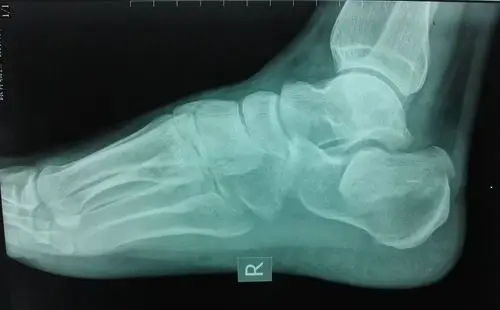

跟骨骨折病例

双侧跟骨骨折

这个跟骨可以接受吗

脚跟粉碎性骨折.那位大神会看x.ct片子?帮我看看,骨折了吗?治疗方案.

这6张跟骨图像你能分得清吗